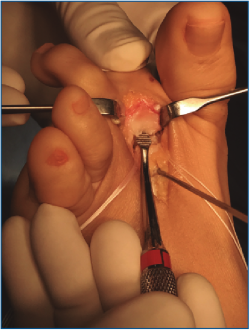

2. Luxamos el dedo a plantar y despegamos cuidadosamente la placa plantar del cuello metatarsal con un periostotomo o un disector de McGlamry (Figura 2).

Figura 2. Movilización cuidadosa de la placa plantar con disector de McGlamry.